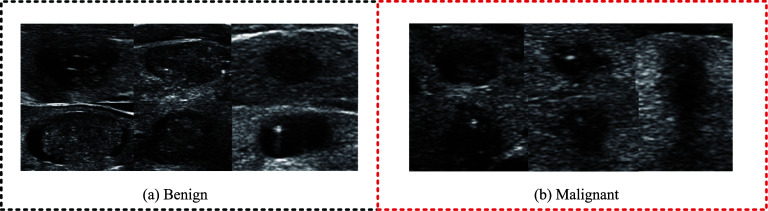

Thyroid cancer represents the most prevalent form of endocrine malignancy [1]. Improving the identification and detection of thyroid nodules has become a crucial strategy to prevent this disease. However, evaluating thyroid nodules poses a significant challenge in the clinical setting. Currently, cervical imaging techniques such as ultrasound constitute the primary means of identifying or detecting thyroid nodules [2]. Ultrasound imaging has long been used as a screening method for the clinical diagnosis of thyroid nodules. The radiologist also proposed a guideline for thyroid nodule characteristics based on ultrasound images [3], and identified some ultrasound characteristics of thyroid nodules as indicative of malignancy, including low echo, no halo, microcalcification, solid component, flow within the nodule, and high-width shape [4]. Based on these features, radiologists have also devised a specialized thyroid Imaging Reporting and Data System (TI-RADS) for classifying thyroid nodules and stratifying their risk of malignancy for use by radiologists [5]. However, evaluating thyroid nodules using TI-RADS is time-consuming and limited by the imaging mechanism of ultrasonic images. Medical ultrasound images are characterized by low contrast and significant noise interference, as shown in Fig. 1. As a result, ultrasound diagnosis often depends on the experience of radiologists [6]. Inexperienced doctors may not be able to accurately interpret ultrasonic characteristics, leading to a high rate of misdiagnosis. Misdiagnosis can result in unnecessary biopsies, causing undue stress and anxiety.

Fig. 1.

Thyroid nodules: a Benign nodules; b Malignant nodules